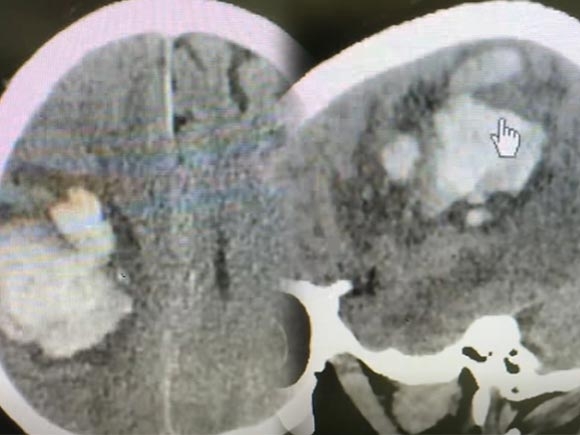

มีอาการไม่พูดจนคิดว่าผีเข้า สุดท้ายกลายเป็นโรคร้ายแรง ไม่ต้องแขนขาอ่อนแรงก็เป็นได้